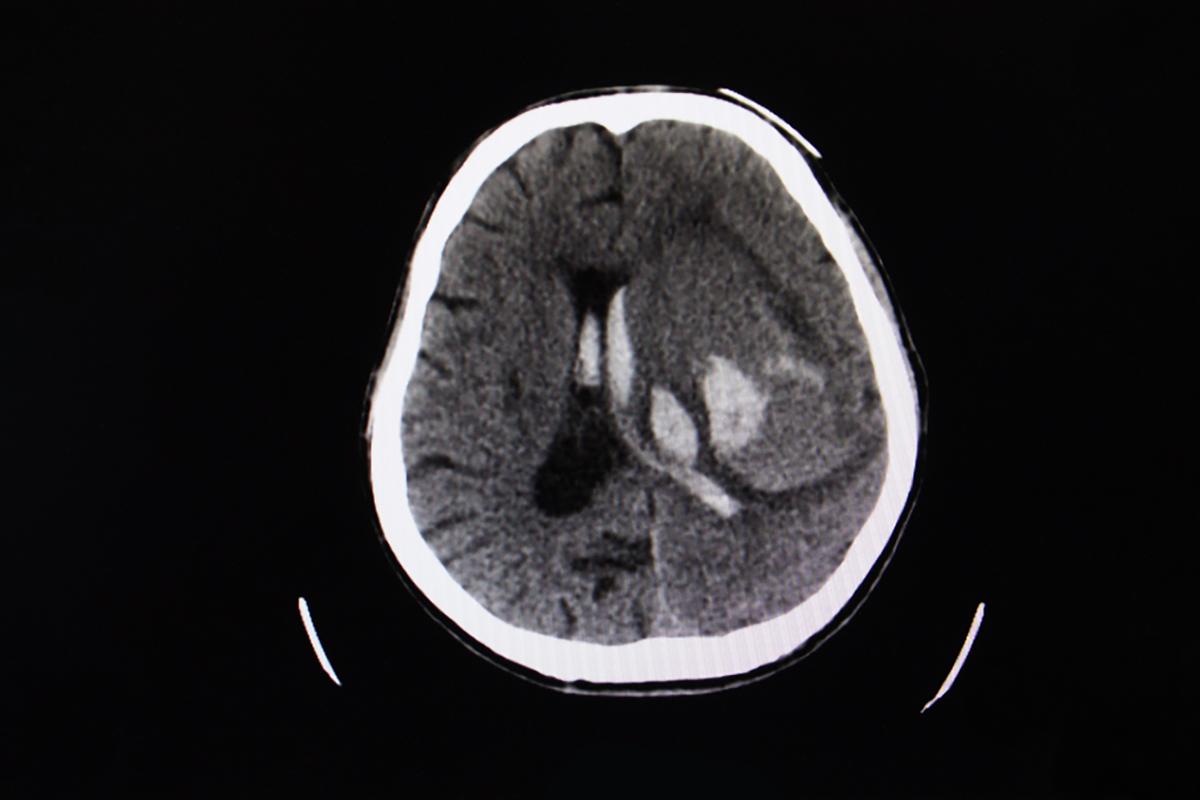

水腦症

水腦症會好嗎?嬰兒與老人症狀差異、壽命、治療